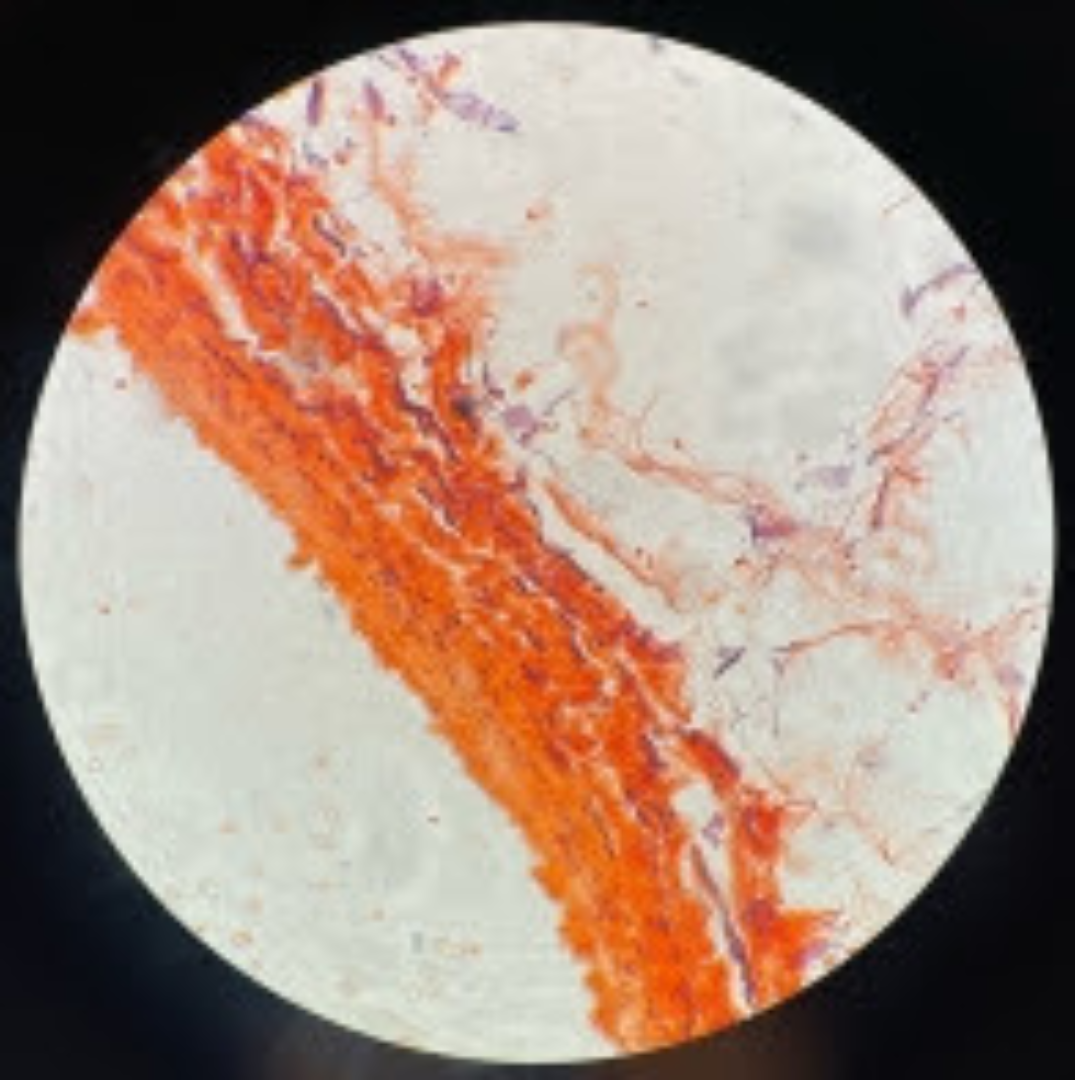

Dense Regular Elastic Connective Tissue (Elastic Tissue)